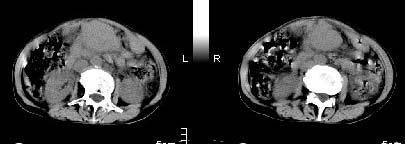

胰腺受压前移,胰管扩张,应为腹膜后占位,病灶密度不均,有低密度坏死区,强化扫描强化不明显腹腔干动脉受侵,考虑腹膜后恶性占位

从发病部位(腹主动脉周围)及增强方式(均匀轻度强化、少量坏死)和病变形态(较大、多结节形)符合腹膜后淋巴瘤,建议颈部病变活检。

我的第1诊断还是考虑是淋巴类病变1}。从病灶形态上看不是很规则,但其更向是多个结节的融和,其内有少许坏死,整个病灶的强化不是很明显,临近左恻肠间隔有增厚,2}我认为更重要的一点的是肠系膜有明显增厚呈片状。3}患者的脾脏不大其未见异常病灶。结合以上几点我首先考虑是转移性{但对此诊断我觉得不足之处;转移性的淋巴结肿大融合为什么没有坏死?}。{另外患者无大便习惯改变及血便,其发现右颈包块在今年过年无意发现}。以上是我的浅分析望各位战友继续讨论!谢谢!!